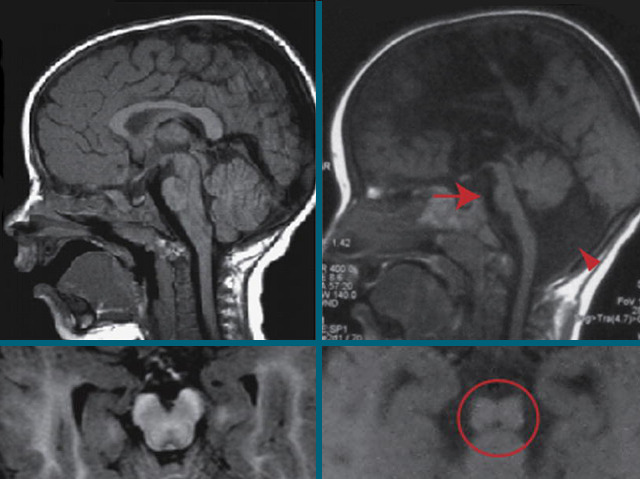

Neurodegenerative diseases, where structures in the brain break down, are devastating for the people affected and their loved ones. These include Parkinson’s, Alzheimer’s and Huntington’s diseases in adults, but there are also others affecting very young children. Babies born with an inherited fault in a gene called AMPD2 have difficulties with feeding and movement after birth, which get progressively worse. Sadly, they usually die by the age of ten and there is no treatment. The faulty gene causes problems with their brainstem – a key area that links movement and sensing signals between the brain and the body. The difference is clear in the brain scan on the right where a patient’s shrunken brainstem is highlighted in red, compared with an unaffected child on the left. The good news is that researchers are working on drugs that could over-ride the loss of AMPD2 and provide hope for children in the future.